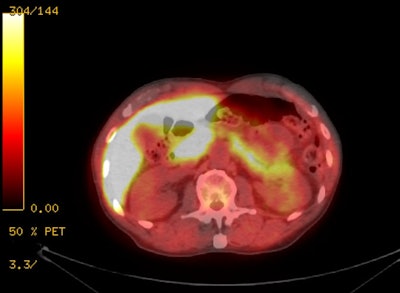

FDG PET in prostate cancer:

FDG PET imaging is generally not useful for the diagnosis of

primary prostate cancer primarily due to low glucose metabolic

rates and low FDG tumor uptake [6]. Urinary bladder activity also

interferes with exam interpretation [2,4]. Additionally, there is

overlap in uptake values with benign prostatic hyperplasia [6] and

false positive exams can be seen in patients with prostatitis

[25]. However, patients with higher primary tumor uptake had a

significantly worse prognosis than do patients with lower FDG

uptake [62].